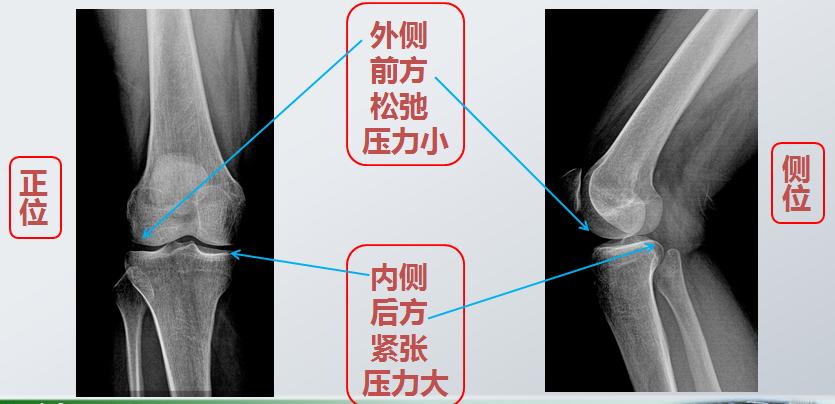

首先,膝关节的磨损最早发生于后内侧

这是因为关节面受力不均的原因

这就是关于膝关节炎的第三个问题

膝关节后方的肌肉

就像两只手相互交叉拉紧锁定

再加上久坐,膝关节长时间处于屈曲位

后方很容易发生紧缩

所以腘绳肌和腓肠肌都需要拉伸

而前方的肌肉(股四头肌)易出现松弛、乏力

需要加强力量训练

肌力的不均衡不只会带来疼痛

而且由于内侧过紧,

还可能导致“O”型腿的发生

这也是关节炎后期膝关节最常见的畸形